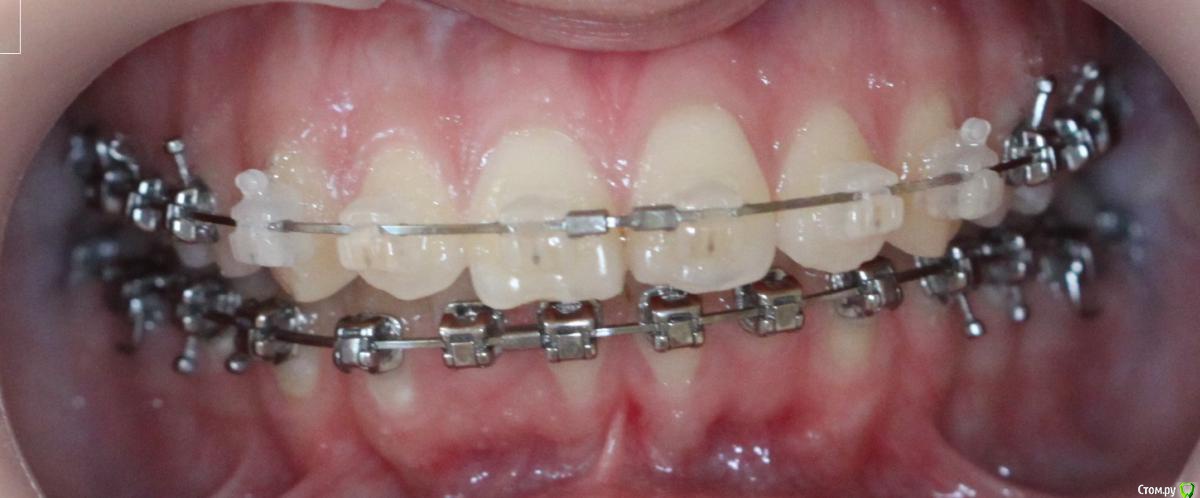

annurka Опубликовано 12 сентября, 2017 Поделиться Опубликовано 12 сентября, 2017 (изменено) здравствуйте! 24 года, дисфункция ВНЧС, дистальный прикус (1,4см), ортодонтическое лечение начато с ношения каппы для разгрузки сустава (привыкла подтягивать НЧ к верхней) в 2012 году. проведено лечение: удаление всех 8к (непрорезавшиеся), расширение ВЧ (аппарат дерихсвайлера), выравнивание зубных рядов, сепарация нижних резцов (резцы были наклонены), места не хватило - удаление 2 нижних 4к, выравнивание кривой шпее, двухчелюстная остеотомия; выравнивание окклюзионных контактов (резиновые тяги) проблема: между верхними и нижними резцами расстояние 5мм к трг (внизу фото) есть расшифровка.все идет к снятию брекетов, и с эстетической точки зрения меня все устраивает. но не до конца устраивает в функциональном плане (я не могу пропихнуть палец между зубными рядами, как раньше, но все также подтягиваю челюсть кпереди когда ем, говорю)стараюсь контролировать это, но даже улыбнуться не могу не подтянув - иначе у меня некрасиво вырисовывается подбородок, неправильно произношу звуки при разговоре.сразу после остеотомии состыковка резцов была ок - нижние зубы были за верхними, но мы с ортодонтом занялись состыковкой и других зубов (которые тогда не соприкасались), и когда добились контактов жующих сторон, разошлись резцы.UPD: и еще есть черные треугольники на НЧ - с ними тоже очень хочется разобраться лечащий ортодонт говорит, что это в целом норма, с учетом моего случая. и возможно это так, но я очень хочу послушать еще мнений, возможно стоит удалить 2 зуба наверху, чтобы верхняя челюсть подошла по размер нижней? [боюсь что простой сепарации может не хватить и как в случае с нижними резцами придется и сепарацию делать, и удалять зубы.] может быть еще есть другой способ добиться нормального прикуса, без "нюансов"?изначально я пошла на все это лечение, чтобы остановить разрушение сустава (однажды проснулась и не смогла рот даже открыть, еще до лечения), полагала, что брекеты и члх исправят если не ситуацию, то причину, но я все еще двигаю НЧ вперед к ВЧ. с остеотомии прошел почти год (поэтому на изменение картины эластиками я уже не надеюсь), брекеты ношу почти 4 года. заранее всем спасибо за отклик! Изменено 12 сентября, 2017 пользователем annurka 1 Ссылка на комментарий

annurka Опубликовано 13 сентября, 2017 Автор Поделиться Опубликовано 13 сентября, 2017 (изменено) А До лечения есть ТРГ посмотреть? И фото какие-нибудь?есть трг сверху - сразу после остеотомии, снизу - через полгода после (когда резцы отошли друг от друга на 5мм) до лечения вообще точно делал ортодонт (снимки, слепки, фото), если в клинике это сохранили, я смогу сфотографировать. далее фото в процессе лечения - 4ки нижние еще не удалены, один хирург был готов так оперировать, другой сказал, что наклон нижних резцов неправильный и нужно как и было запланировано удалить 4ки, сепарации недостаточно.челюсть расслаблена как есть: НЧ подвинута к ВЧ для наглядности: есть фото слепков того периода, но форум ругается на слишком большой размер. если нужно - уменьшу залью) Изменено 13 сентября, 2017 пользователем annurka 1 Ссылка на комментарий